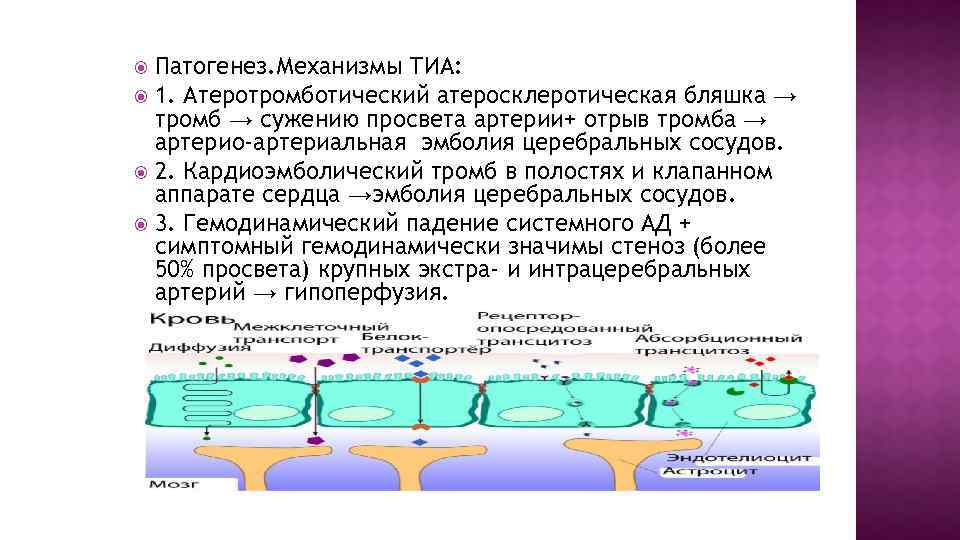

Патогенез. Механизмы ТИА: 1. Атеротромботический атеросклеротическая бляшка → тромб → сужению просвета артерии+ отрыв тромба → артерио-артериальная эмболия церебральных сосудов. 2. Кардиоэмболический тромб в полостях и клапанном аппарате сердца →эмболия церебральных сосудов. 3. Гемодинамический падение системного АД + симптомный гемодинамически значимы стеноз (более 50% просвета) крупных экстра- и интрацеребральных артерий → гипоперфузия.

Патогенез. Механизмы ТИА: 1. Атеротромботический атеросклеротическая бляшка → тромб → сужению просвета артерии+ отрыв тромба → артерио-артериальная эмболия церебральных сосудов. 2. Кардиоэмболический тромб в полостях и клапанном аппарате сердца →эмболия церебральных сосудов. 3. Гемодинамический падение системного АД + симптомный гемодинамически значимы стеноз (более 50% просвета) крупных экстра- и интрацеребральных артерий → гипоперфузия.